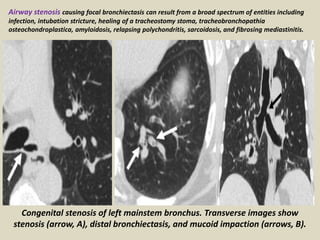

Congenital stenosis of left mainstem bronchus. Transverse images show

stenosis (arrow, A), distal bronchiectasis, and mucoid impaction (arrows, B).

Airway stenosis causing focal bronchiectasis can result from a broad spectrum of entities including

infection, intubation stricture, healing of a tracheostomy stoma, tracheobronchopathia

osteochondroplastica, amyloidosis, relapsing polychondritis, sarcoidosis, and fibrosing mediastinitis.